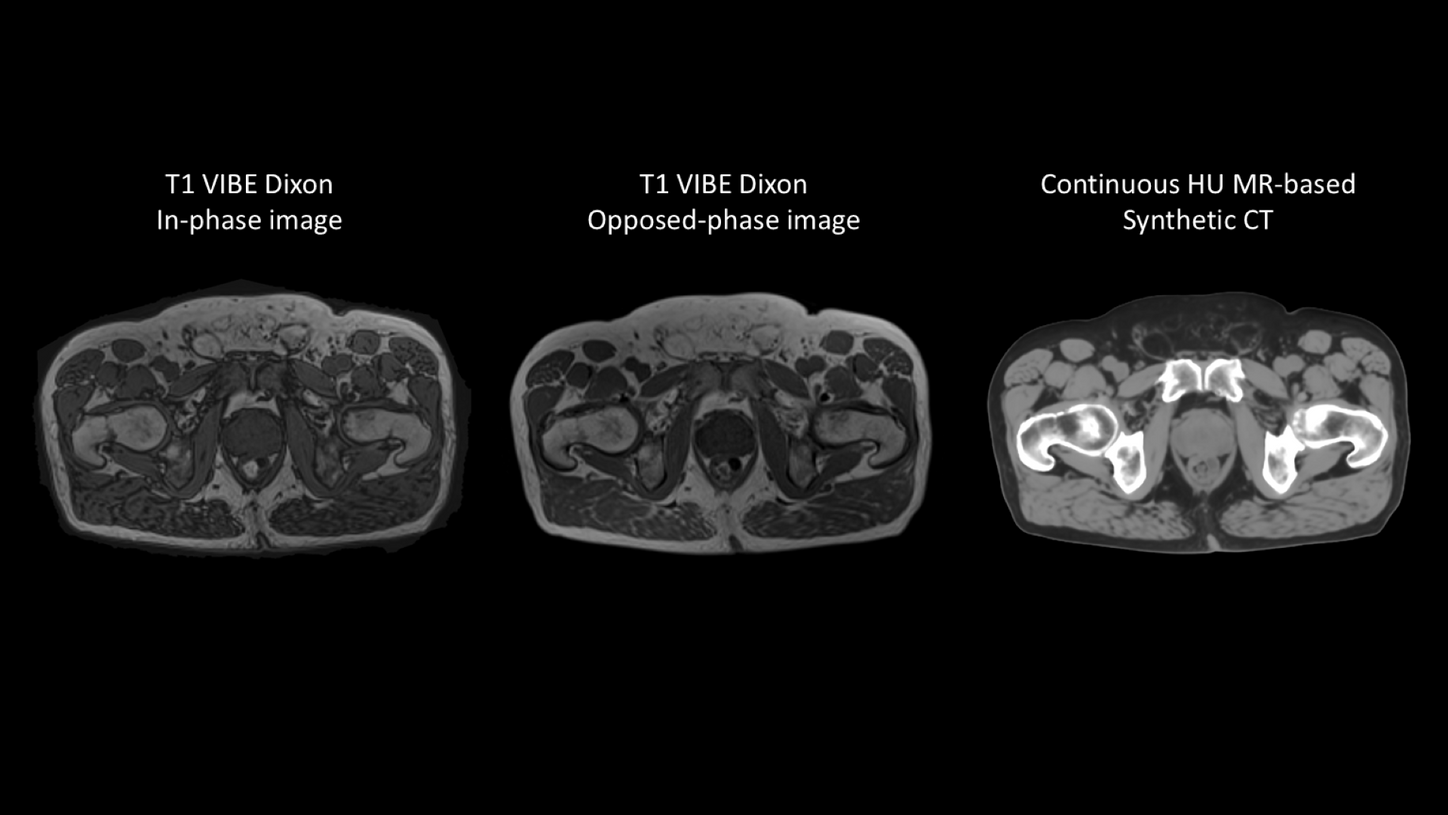

While MR provides excellent soft-tissue contrast and functional information, CT is still required for electron density information for accurate dose calculation. As a result, many institutions have to adapt their RT treatment planning workflow, in which patients are normally scanned on both imaging modalities. Fusing CT and MRI modalities makes the workflow more complicated and adds uncertainties in the planning process.1, 2

MR-based Synthetic CT offers the possibility of combining the superior soft-tissue contrast of MRI for organs-at-risk and target delineation with dosimetric planning. An MR-only workflow eliminates the need for CT to MRI registration, reducing systematic registration errors and unnecessary ionizing radiation from CT scans.